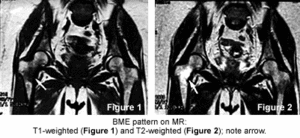

So, we have several terms that describe a process that may represent a spectrum of disease. Thus, depending on when the condition is first diagnosed, we may describe it with one term but later with another. Because they are all self-limiting conditions usually resolving within a two-year period, it may not matter which term is used, as long as it is differentiated from osteonecrosis (which is progressive and carries serious complications). Unfortunately, all these conditions present with bone marrow edema identified with the use of MRI, which is 100 percent sensitive but not specific. The edema seen with BMES usually is more extensive than that seen with osteonecrosis. The bone cortex may appear thinned but always is intact. Unlike osteonecosis, there should be no evidence of subchondral defects. Osteonecrosis of the hip is progressive, resulting from an interruption of the vascular supply to the femoral head and can lead to the collapse of the femoral head, destruction of the hip joint and necessitates aggressive intervention early in the disease process.